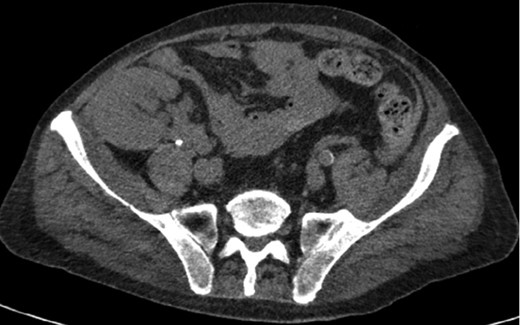

Axial CT imaging of the pelvis demonstrating heterogeneous fluid (blood) in the pelvic small bowel mesentery. Also shown is the patient’s renal transplant with clear perinephric fat planes. The renal graft was grossly uninvolved and viable appearing at the time of laparotomy.